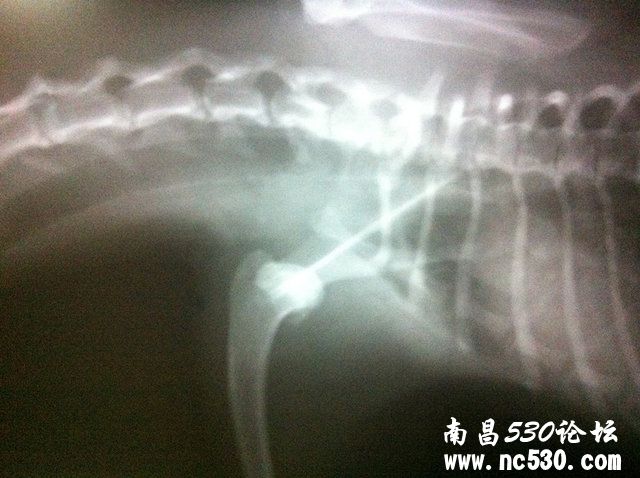

我家狗狗两天前晚上在家里浴室洗澡时,从平台上跳下滑倒摔伤。此后不能正常站立和行走,左前肢不着地。今天去医院拍X光检查,显示左前肢肩关节脱位(如下图)。医生转动前肢和夹脚趾时狗狗均有痛感。请问是否有可能不打开手术,而是手工进行复位后再固定?担心麻醉对狗狗身体伤害太大。多谢医生!

泰迪左前肢肩关节脱位